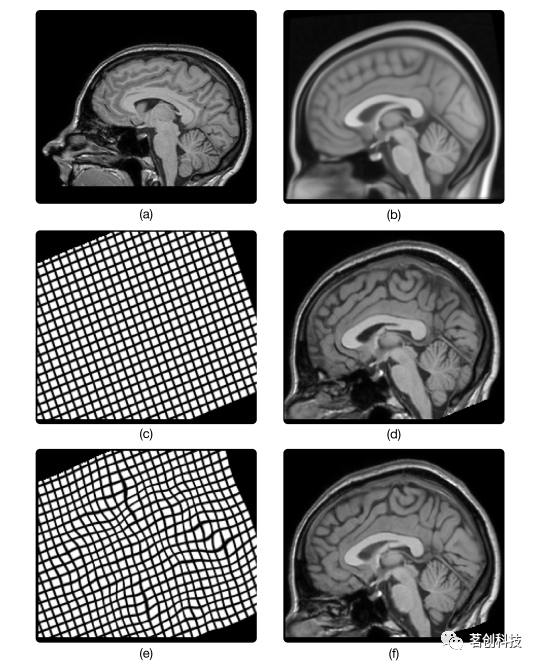

早在20世纪40年代数字革命开始之前,图像配准就已经成为一个具有重要现实意义的过程。这技术首次应用于彩印,即将几种单色图案叠加在一起形成多色图案。为了生成最终所需的多色印刷品,各个层相对于另一个层的对齐必须是精确的。若个别层发生错位,称为失配。因此,为了确保准确的配准,人们开发了检测和校正任何偏差的流程。随着数字革命开启了现代医学成像时代,图像配准已经成为医疗成像研究中不可或缺的工具。虽然MRI不